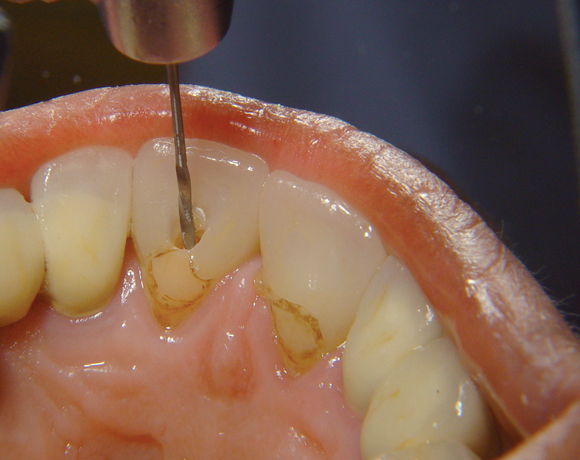

Der Dentinpost Stift ist die Antwort auf den zu harten Cerapost Stift, er ist aus Glasfaser und damit der Härte des Wurzeldentins angepasst.

Bei diesem Patientenfall musste nach Neuüberkronung der Frontzähne eine Wurzelbehandlung erfolgen. Um der Gefahr aus dem Weg zu gehen, dass die neue Krone abbricht, da sehr wenig eigene Zahnrestsubstanz nach der endodontischen Behandlung übriggeblieben war, wurde der Zahn nachträglich mit einem Dentinpost versorgt.